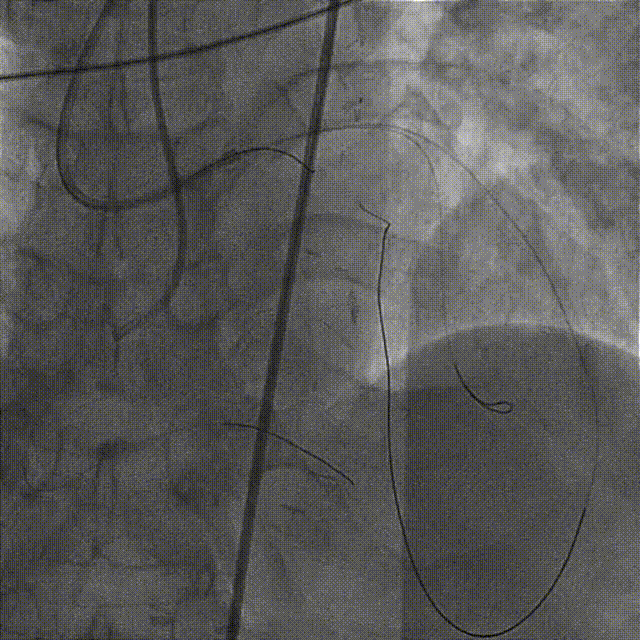

造影示支架定位良好,D1开口受压90%狭窄,交换一根SION导丝穿支架网眼至D1远段,用Pinoeer1.5mm x 15mm、Pinoeer 2.0mm x 15mm球囊至D1开口处扩张。

FOXTROT NC 2.5mm x 15mm、FOXTROT 3.0 mm x 15mm后扩球囊后扩球囊至支架内后扩,以实现支架的充分贴壁,并对LAD远段进行球囊扩张,造影显示TIMI血流III级。

术后行IVUS检查示:支架定位贴壁扩张良好,LAD开口MSA:7.43mm2。